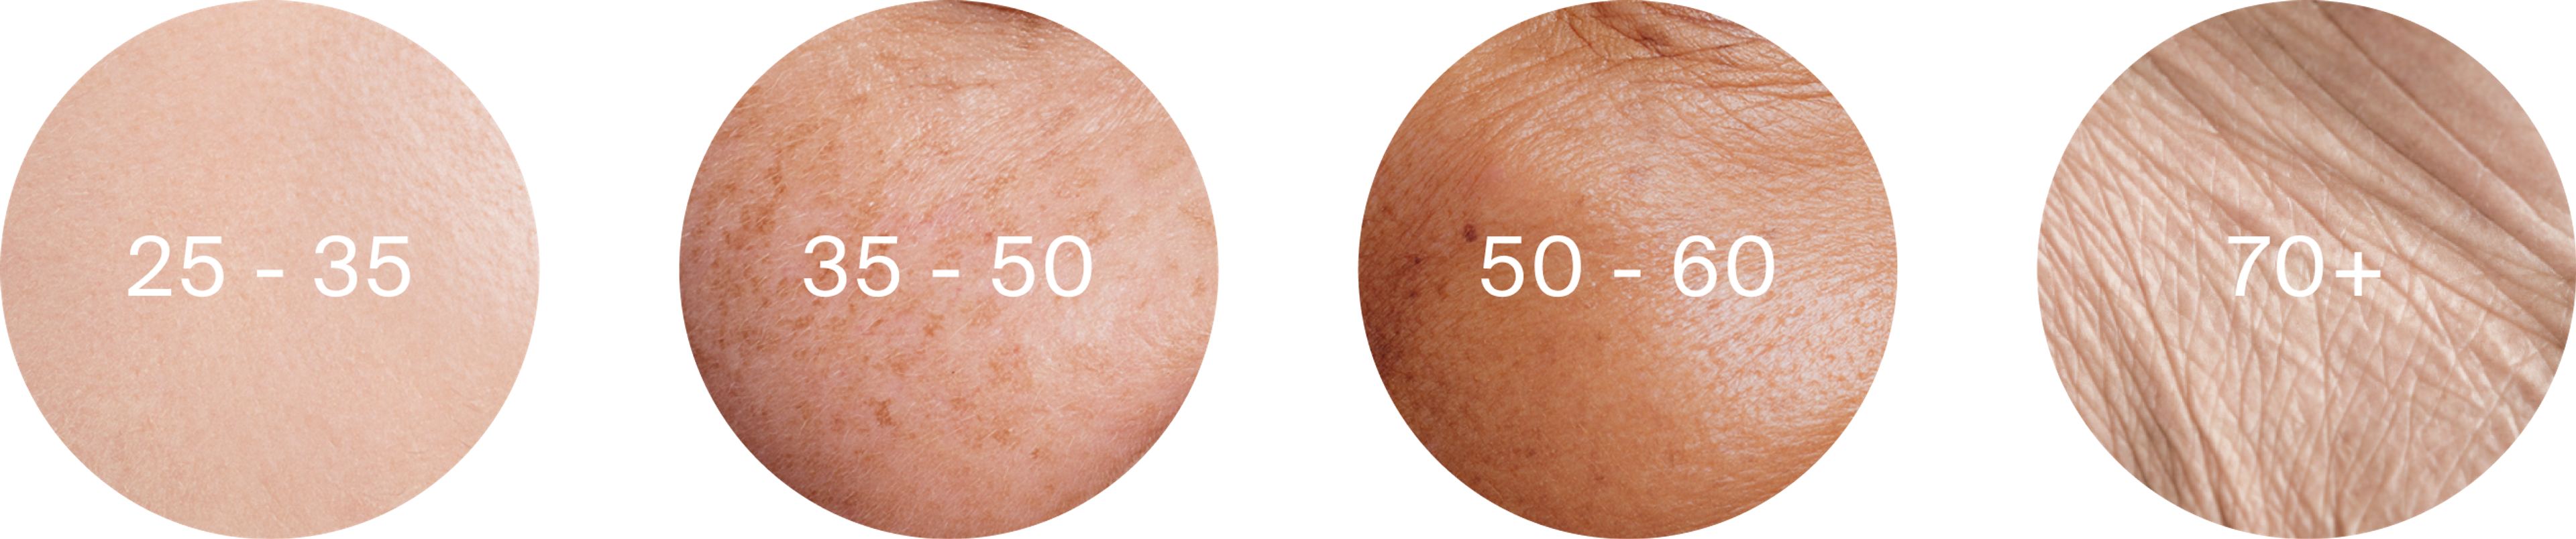

The evolution of skin through the years

It is not easy to predict the “schedule” at which our skin will age, in part because this greatly depends on nutrition, lifestyle, and skin health-related habits. That said, dermatologists and cosmetic specialists do agree on a rough timetable for stages of skin aging:[10]

Skin evolution through the years

Age 25 - 35: The early signs of aging can start to appear, with fine lines linked to facial expression, and the early signs of crow’s feet. Collagen and elastin production can start to slow down, and the skin begins to lose the radiance it once had.

Age 35-50: Changes in skin thickness and elasticity become more noticeable. Fine lines and wrinkles appear at rest. Larger pores may appear, some may notice the development of bags underneath the eyes. The cheeks sag as they lose volume. Some may notice lines, wrinkles and sagging under the chin and in the neck area. The signs of earlier sun-damage may start to appear.

Age 50-60: More pronounced changes become visible due to further slow down in collagen and elastin production. Bone mass may also have started to reduce, which can change the contours of the face. Gravity is taking more of an effect, causing the skin to hang, and maybe even pulling the nose downwards. The skin starts to be thinner and more fragile. Wrinkles may be present on the entire face at rest. The next stage.

Age 70+: Wrinkles are marked and deep. The cheeks and skin on the edges of the chin, along with around the eyes and eyelids may sag. Age spots due to sun damage will be visible. Around the eyes, cheeks and foreheads the wrinkles may develop a “crisscross” pattern.